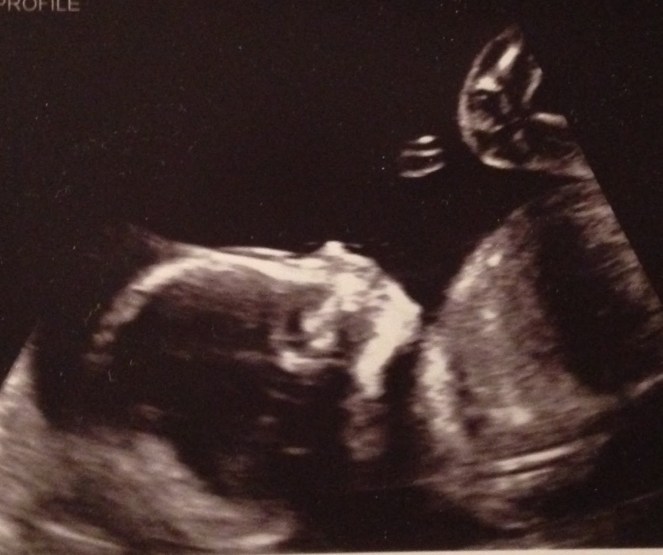

This is my daughter at just under 20 weeks. She has all human likeness and all her major organs are functioning. They are still developing, but they are there and functioning. At this ultrasound, my husband and I laughed as we watched our baby jump, dance, twirl, play with her hands, open and close her mouth, and live. She was clearly a human being independent from me. This is not my body.